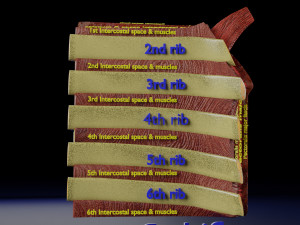

This is a 1:1 scaled model of right breast cut opened in sagittal plane to reveal its internal antomy and histology (schematic). The deeper parts and fascial layers are also depicted to give a very detailed approach to the model. The full layers starting from skin, nipple areola, till intercodtal muscles and ribs are also depicted.